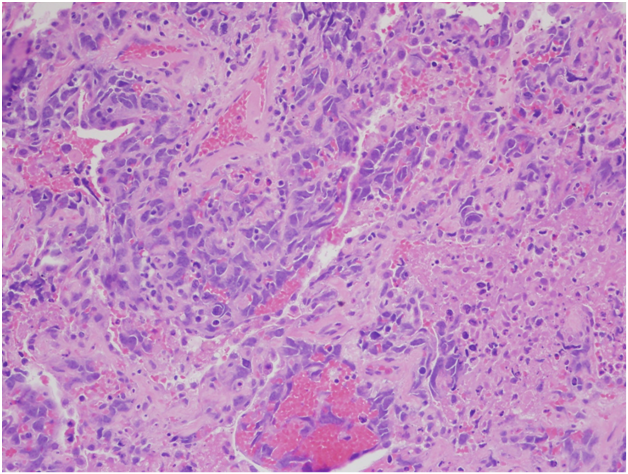

However, the wedge resection of the right lower lobe revealed angiosarcoma with lymphovascular invasion. This biopsy showed highly atypical and large malignant cells with increased mitoses (Figure 2A&2B). The immunohistochemical stains showed diffuse positivity for CD31, CD34, and vimentin (Figures 3A-3C). Stains for AE1/AE3 (Figure 3D), cam5.2, TTF-1, desmin, and OCT3/4 were negative. Along with the clinical history, a final diagnosis of angiosarcoma of the heart with metastases to the lungs was made.

Figure 2A Right lower lobe wedge resection. H&E, 200x

Figure 2B Right lower lobe wedge resection. H&E, 400x